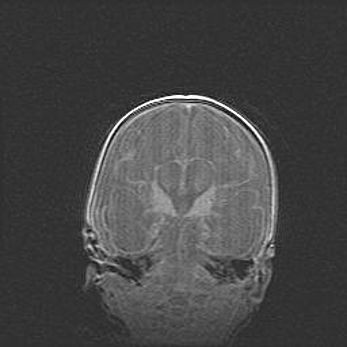

Сообщающаяся гидроцефалия. Кистозная энцефаломаляция головного мозга.

Возраст: 3 месяца 4 дня

Вес: 3100 г

Пол: женский

Окружность головы: 34 см

Срок гестации: 31 неделя

Кистозная энцефаломаляция головного мозга - одна из форм поражения головного мозга в детском возрасте. Характеризуется возникновением множественных и распространённых кист в коре, белом веществе и подкорковых образованиях головного мозга у плодов, новорождённых и детей раннего возраста. Развитие кистозной энцефаломаляции связано с внутриутробной асфиксией и гипотонией, родовой травмой, тромбозом синусов, пороками развития сосудов, инфекциями, сепсисом и другими причинами. Наиболее значимые инфекционные агенты: вирусы простого герпеса, цитомегалии, краснухи, токсоплазмы, энтеробактерии, золотистый стафилококк и другие.